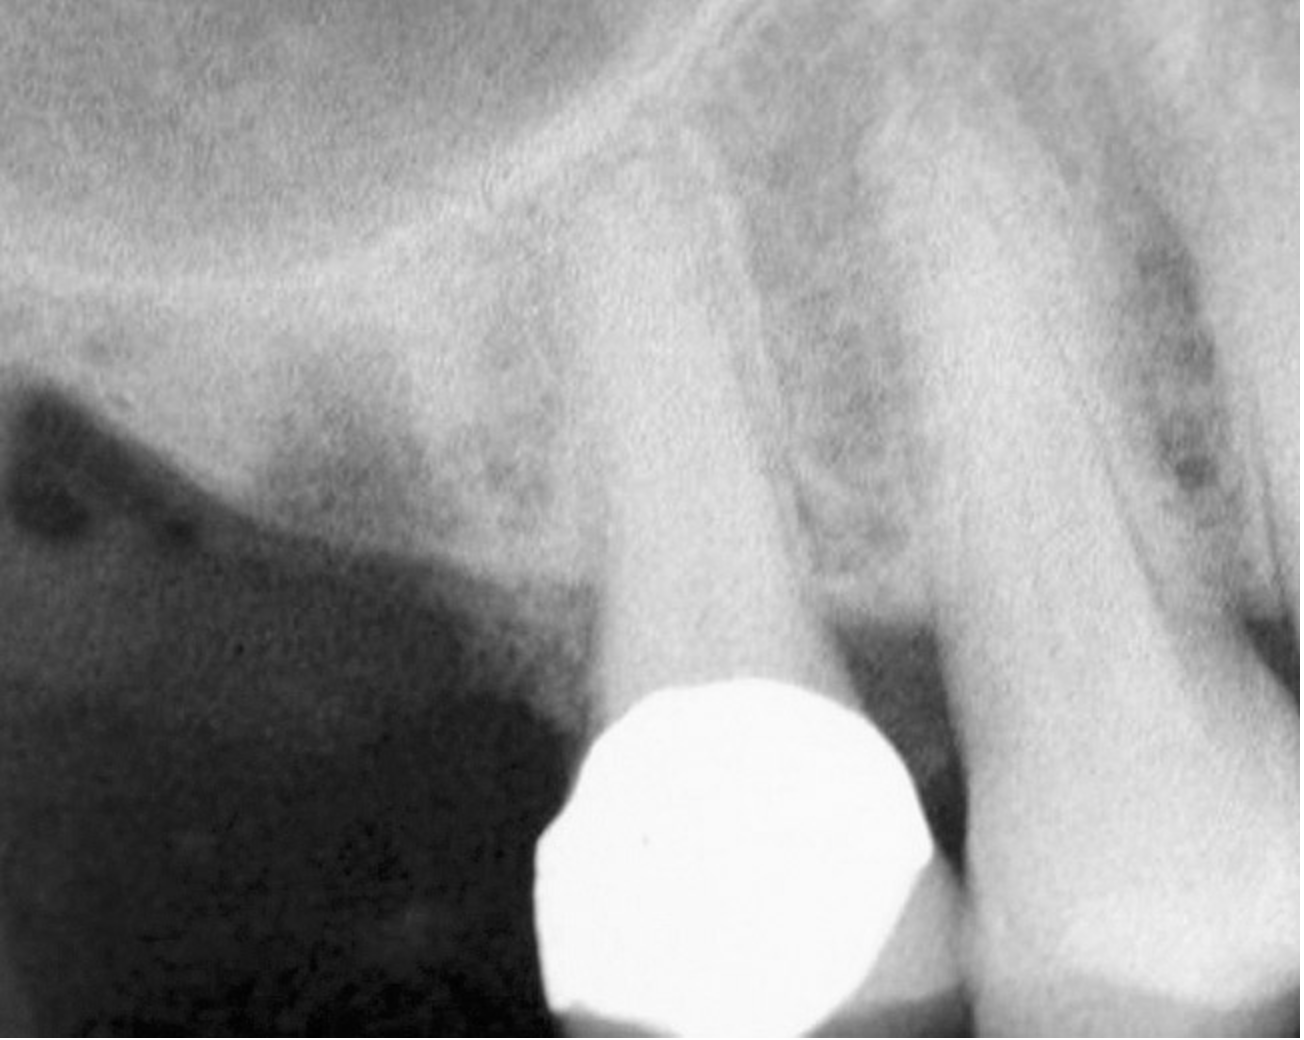

Figure 15  Implant successfully placed.

Figure 15